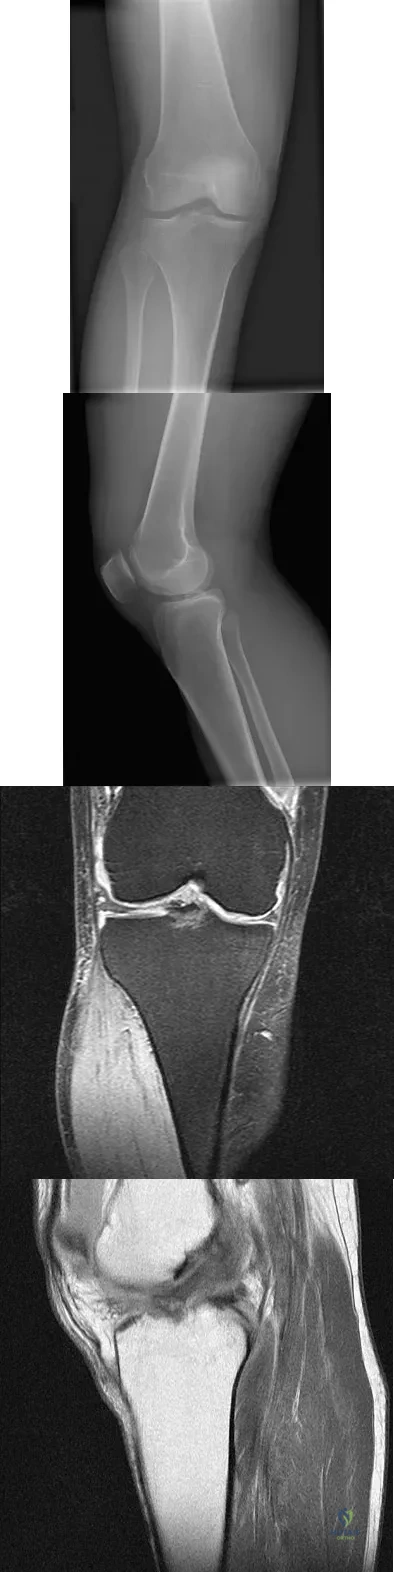

Question 76

A 23-year-old woman falls from a bicycle and sustains a right knee injury. Figures 12a through 12d show radiographs and MRI scans of the knee. What is the most likely diagnosis?

Explanation